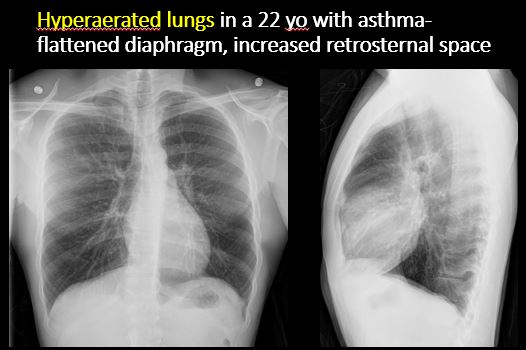

The lungs are hyperinflated or underinflated generally or segmentally. [Yes/No]

There is elevation, depression, or contour abnormality of the right or left hemidiaphragm. [Yes/No]